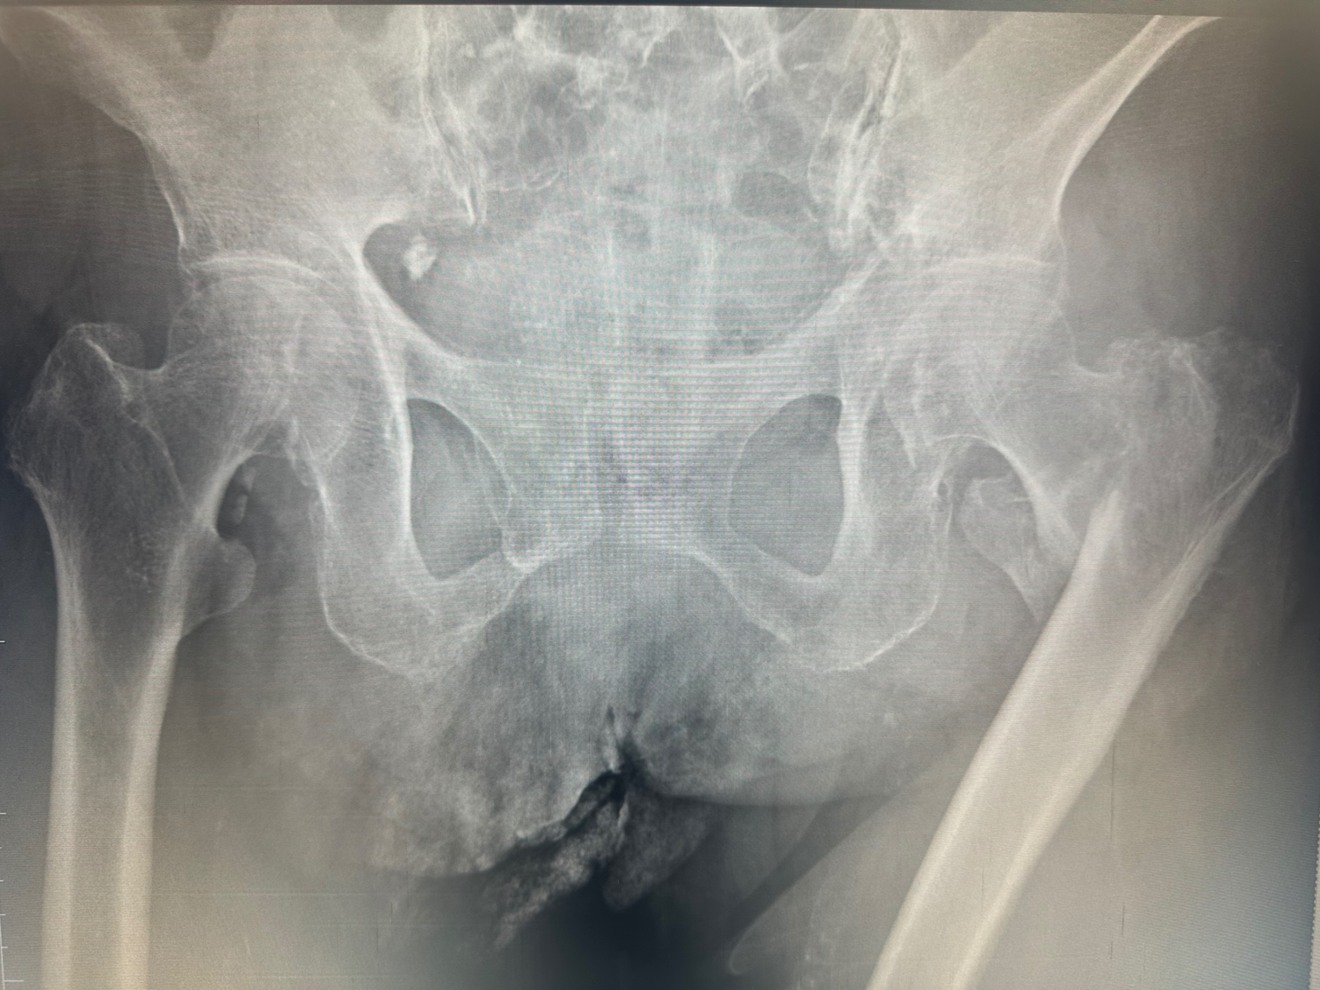

å€§è ¿éªšè¿äœéšéªšæ(倪ããã®ä»ãæ ¹ãè¡é¢ç¯ã®éªšæ)

転åã«ããèã®ä»ãæ ¹ãæããçã¿ã§æ©ãããšãã§ããªããªããŸãã

æ²»çã¯æè¡ãããªããã°æ©ãããšã¯ã§ããªããªã£ãŠããŸããŸãããŸãæè¡ãããŠãå€ãã®æ¹ãæ©è¡èœåãäœäžããŠããŸããŸããïŒå

éãæ©ãããšãã§ããªããªããæãæ©è¡åšãå¿

èŠã«ãªã£ããããããã§å¯ãããã«ãªã£ããïŒ

ãããã®éªšæãèµ·ãããšå ã«è¿°ã¹ãããã«åããªããªããŸããå Žåã«ãã£ãŠã¯æ©è¡èœåã®äœäžã«ããèªå® ã§ã®ç掻ãå°é£ãšãªãããšã§ããã®ãŸãŸæœèšã«å ¥æããããšã«ãªãã±ãŒã¹ãå°ãªããããŸããã